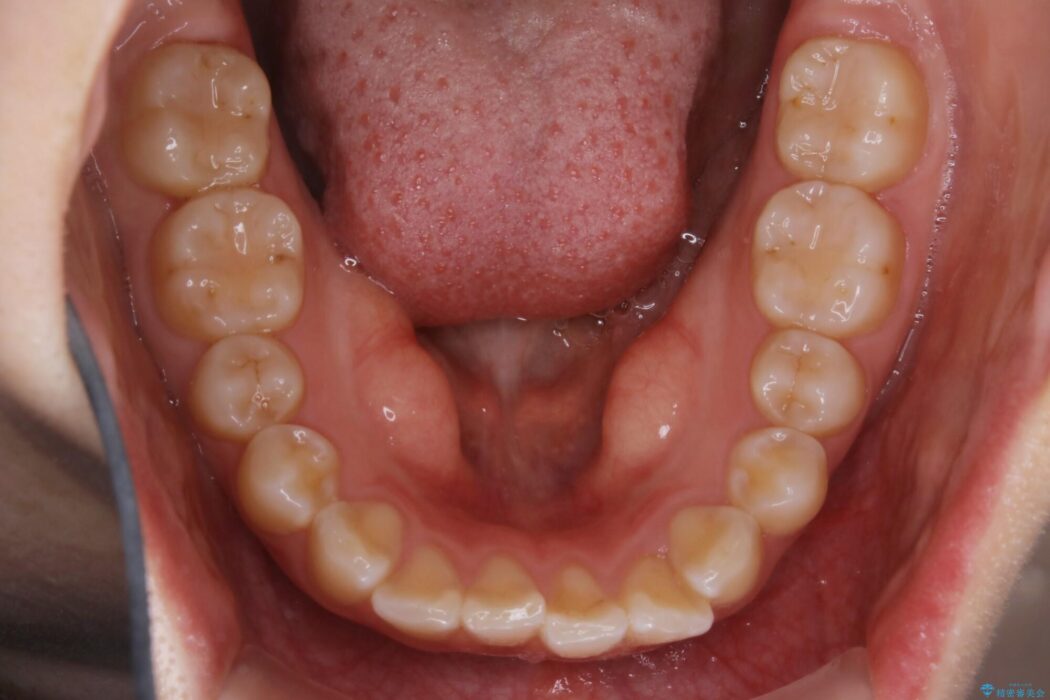

噛み合わせの違和感と前歯のガタガタを主訴に来院されました。

歯軸傾斜と軽度の叢生が見られましたので、通常の位置へと傾きを戻し少量の遠心移動に加えアーチ(歯列弓)の拡大とIPRを施すことで改善していく非抜歯での治療計画としました。